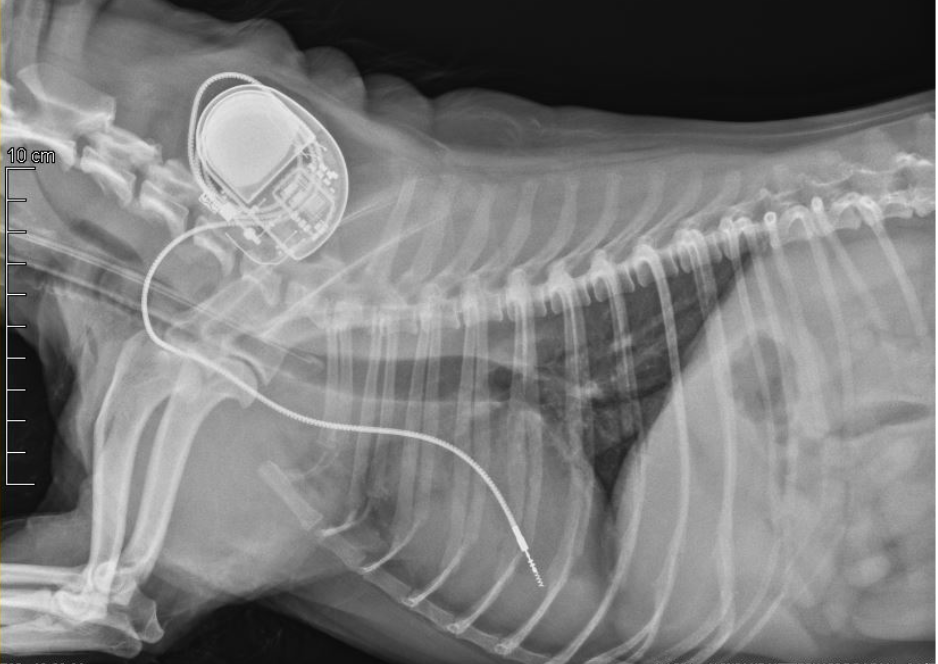

pose de PACE-MAKER

A quoi sert un pacemaker?

Un pacemaker est un dispositif assimilable à une pile placée sous la peau de l’animal, et qui vient remplacer la fonction électrique cardiaque lorsque celle-ci est défaillante.

Techniquement, une électrode relie le boîtier de la pile à la surface du cœur. Cette électrode capte les battements cardiaques naturels et envoie une décharge électrique lorsque ceux-ci sont absents ou inappropriés.

Au Centre Hospitalier Vétérinaire HOPia, nous proposons la pose de pacemaker par voie endovasculaire en priorité. Le pacemaker est placé sous la peau du cou et l’électrode est avancée dans le cœur via la veine jugulaire (Photo). La chirurgie est courte, limitant le risque anesthésique. L’animal est généralement hospitalisé en ambulatoire et rentre au domicile le soir même. La récupération postopératoire est rapide puisque les douleurs sont minimes.

Dans de rares cas, la pose par thoracotomie (ouverture du thorax) est indispensable (petits gabarits, infection de la peau, maladies hormonales…). Dans ce cas l’électrode est fixée sur la partie externe du cœur en chirurgie. L’animal reste alors hospitalisé environ 3 jours.

Le Centre Hospitalier Vétérinaire HOPia utilise des pacemaker neufs Medtronics® développés pour l’homme, dotés d’une capacité de batterie d’une dizaine d’années. Pour les propriétaires dans le besoin, le Centre Hospitalier Vétérinaire propose, lorsque les stocks le permettent, l’utilisation de pacemaker reconditionnés.